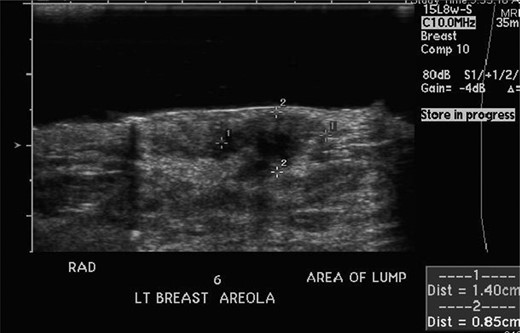

She returned to clinic later in January after the ultrasound, which revealed a 1.4 × 0.9 × 1.8 cm fluid collection at the 6 O'clock position most likely representing a hematoma; BIRADS #3 likely benign recommend short-term follow-up. She was scheduled for a repeat ultrasound in April 2012 with follow-up in breast clinic following the ultrasound. Repeat ultrasound (seen in Fig. 2) revealed a stable fluid collection measuring 1.5 × 1.2 × 2.2 cm, once again BIRADS #3 likely benign recommend short-term follow-up with the breast surgeon. She was seen in clinic following the ultrasound in April and reported decreasing pain and no nipple discharge, she was given a 1-month follow-up appointment.